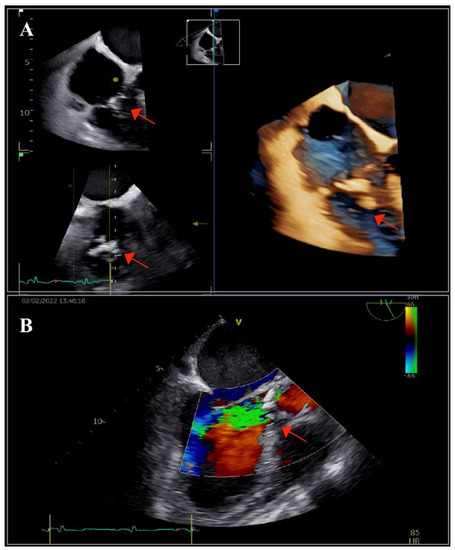

The patient underwent transthoracic echocardiography, which revealed severe aortic and tricuspid regurgitation, moderately reduced left ventricular ejection fraction (35%) and preserved right ventricular systolic function. There were multiple small mobile masses attached to the aortic valve, indicating vegetations. Because the tricuspid valve was thickened, tricuspid endocarditis was also suspected. These findings were corroborated by transesophageal echocardiography (TOE), which revealed multiple vegetations at the level of both the aortic and tricuspid valves that were better visualized with three-dimensional acquisitions (Figure 1). There were no paravalvular complications. Furthermore, TOE visualized an inhomogeneous mass at the level of the superior vena cava (SVC), prolapsing into the right atrium, indicating the possibility of a fibrin sheath subsequent to the removal of the CVC or thrombus (Figure 2).

Figure 1. Transesophageal echocardiography: (A) bi- and tri-dimensional acquisitions depicting multiple vegetations on the tricuspid valve (arrow) and (B) long-axis view showing the aortic valve with vegetations (arrow) and the severe aortic regurgitation. The left aortic coronary cusp was perforated, which was later confirmed during surgery.